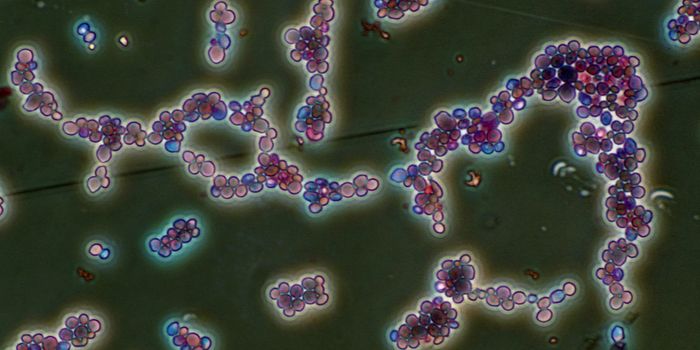

SEP 05, 2024Cell & Molecular BiologyCorynebacterium matruchotii ia a common bacterium that lives in human dental plaque; a colony is seen in this image by S ...